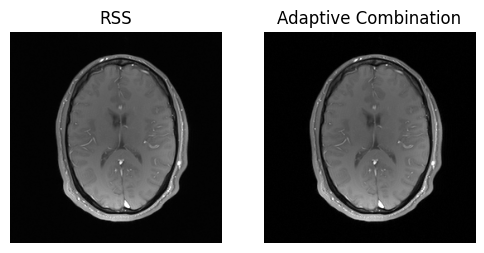

show_images(magnitude_pe_pf, magnitude_walsh_combined, titles=['RSS', 'Adaptive Combination'])

../_images/90fe0c0972b499df54dcb699b3184d46271ef32ab74e034f5ad8c3ba2fa91886.png

Tada! Now we have taken everything into consideration 🎉.